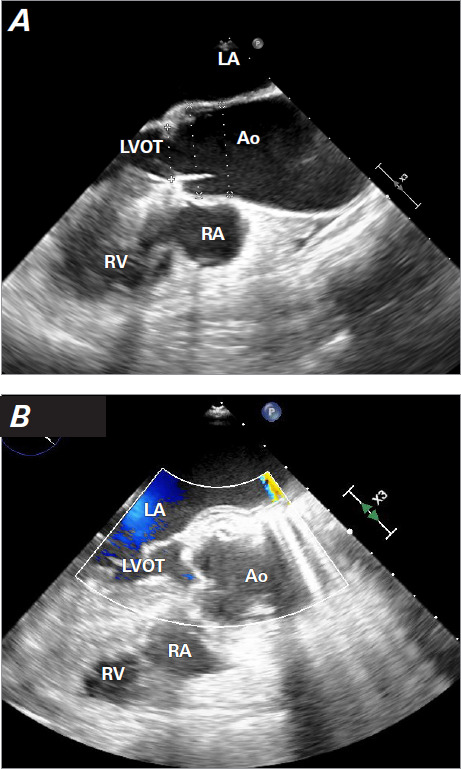

这个新颖的病例记录了一名 75 岁女性患者在修复升主动脉瘤后,成功使用经导管主动脉瓣植入术治疗主动脉根部夹层引起的严重主动脉瓣关闭不全。在她出现充血性心力衰竭症状后,检查发现了新的严重主动脉瓣关闭不全和急性主动脉夹层。考虑到再次手术的风险过高,患者接受了 27 毫米的 Portico(St Jude Medical)自扩张人工主动脉瓣手术,结果临床症状大为改善,且未出现手术并发症。该病例凸显了经导管主动脉瓣植入术在治疗复杂主动脉疾病方面的多功能性,并强调了多学科评估和谨慎选择人工瓣膜的关键作用。

This novel case documents the successful use of transcatheter aortic valve implantation to treat severe aortic insufficiency arising from aortic root dissection following the repair of an ascending aortic aneurysm in a 75-year-old female patient. After she presented with symptoms of congestive heart failure, investigation revealed new severe aortic insufficiency and an acute aortic dissection. Given the prohibitive risks of reoperation, a self-expanding 27-mm Portico (St Jude Medical) prosthetic aortic valve was deployed, resulting in substantial clinical improvement without procedural complications. This case highlights the versatility of transcatheter aortic valve implantation in managing complex aortic disease and emphasizes the critical role of multidisciplinary evaluation and careful prosthesis selection.